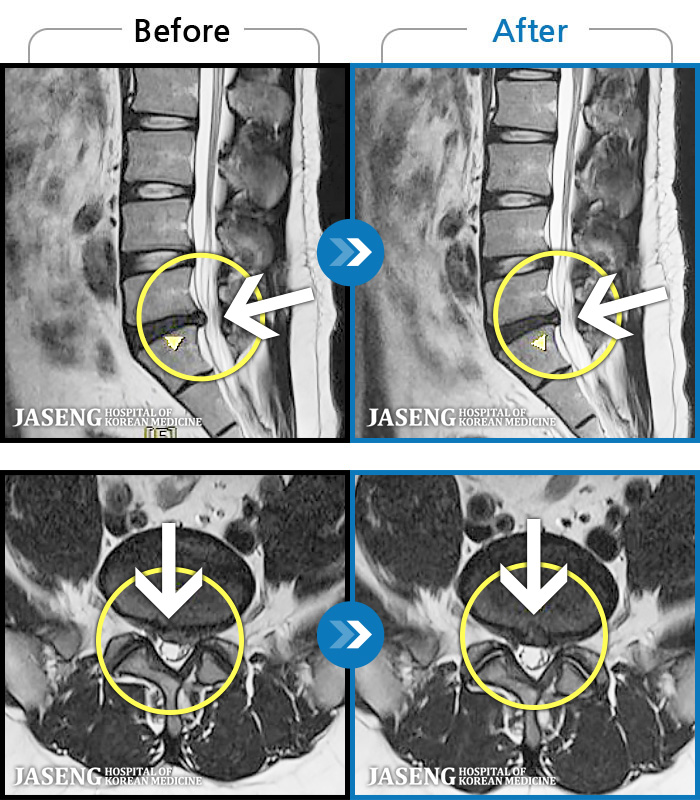

94 MRI ũ ʸ Ȯϼ.

㸮 ϻ .

[Ȼ] 23.03.13~24.05.08

ȯںп Ǹ ǿ ԿǾ, ο ġ ۿ Ƿ ġḦ Ͻñ ٶϴ.